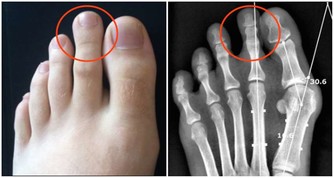

骨密度降低,導致骨骼非常脆弱;